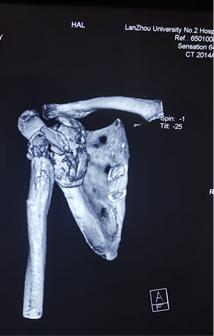

当地医院建议转上级医院治疗,患者以“夏科氏肩关节病”收住科室。患者存在脊髓空洞症,右肩受累关节端硬化更明显,伴骨质增生、破坏、骨膜反应、关节脱位、关节面破坏、塌陷,关节脱位,关节周围软组织肿胀,软组织内不规则钙化斑或碎骨片。关节周围肩袖松弛缺失。

术前X线,肱骨头,肩关节盂缺损严重